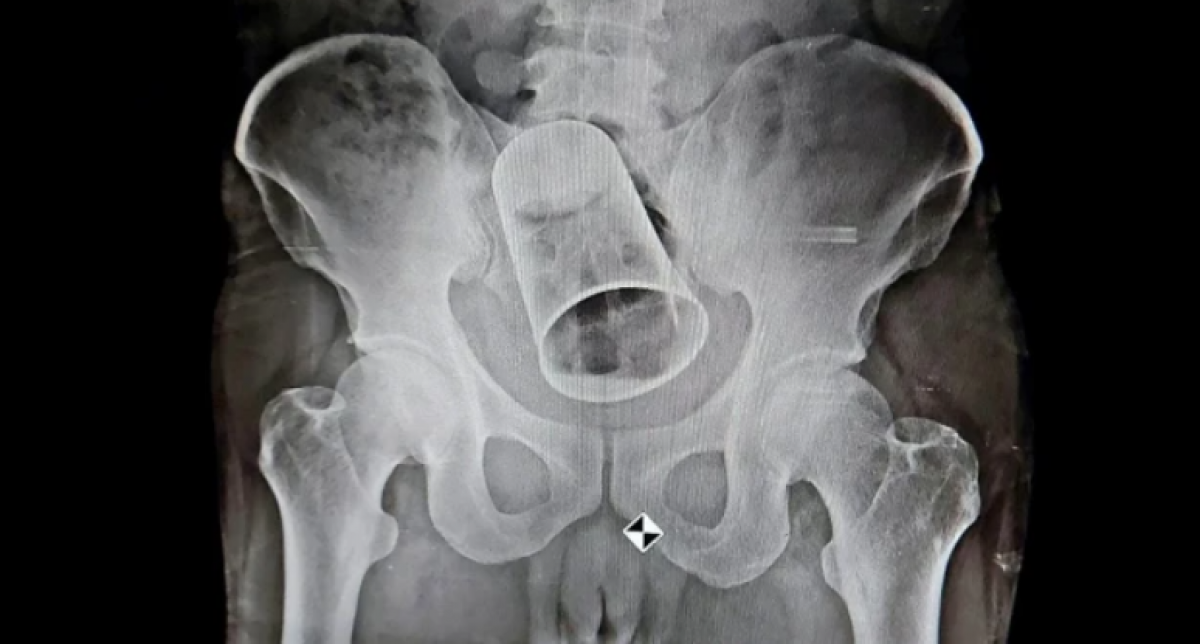

Radiogradía del afectado - Newslions

La copa tenía alrededor de 10 centímetros de diámetro y 15 centímentros de largo, según informes locales, y su intento de quitarla al día siguiente fracasó.

El hombre llegó en estado crítico, y una radiografía tomada en la ciudad de Berhampur encontró que la copa estaba alojada en su intestino, y los médicos tuvieron que cortar el órgano para extraerlo, informa el New Indian Express. El profesor Charan Panda, jefe de cirugía del MKCG Medical College and Hospital, dijo que era el primer caso en el estado en el que se extraía una copa del ano de alguien.